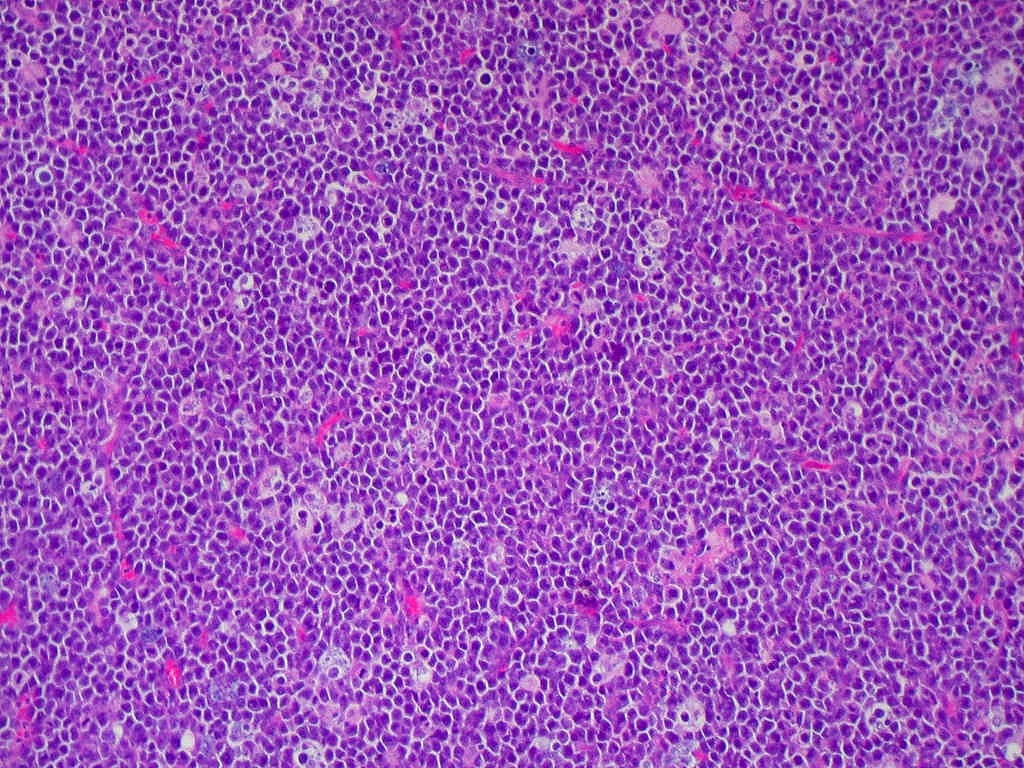

В 1961 году британский хирург Дэнис Беркитт, живущий и практикующий в Кении, приехал в Лондон, чтобы немного развеяться и заодно прочесть пару лекций студентам и коллегам, которые любили послушать рассказы Беркитта о специфике его работы на африканском континенте. В этот раз его выступление было посвящено тому, почему он собирается в ближайшее время отправиться в трехмесячное путешествие длиной десять тысяч миль через шесть африканских стран. На это предприятие, которое позже войдет в историю медицины как «долгое сафари», врача сподвигло то, что вот уже несколько лет он сталкивался с похожими случаями челюстных и брюшных опухолей у детей в своем госпитале. К 61-му году Беркитт описал уже 38 случаев заболевания детей в возрасте до 7 лет и нескольких взрослых. Все они на гистологии напоминали «звездное небо»: среди мелких лимфоцитоподобных клеток разбросаны крупные, со светлой цитоплазмой макрофаги.